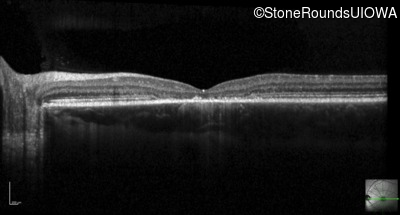

Optical Coherence Tomography - Right - 20/100 -1

Exemplar / OCT Stack

OCT Stack